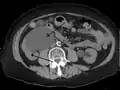

CT scan of bilateral hydronephrosis due to a bladder cancer

Peripelvic renal cysts may look like hydronephrosis on non-contrast CT (left image). However, CT urography (at right) reveals non-dilated calyces and pelvises.